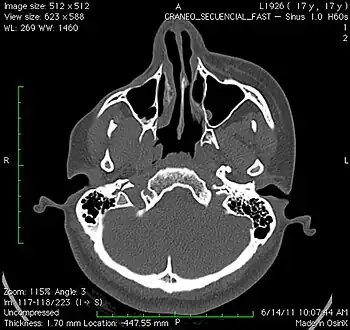

a 17-year-old girl with Parry–Romberg syndrome. The subcutaneous tissue and underlying facial muscles on the right side of the face are severely atrophic, while the left side is unaffected.

Parry–Romberg syndrome (PRS) is a rare disease characterized by progressive shrinkage and degeneration of the tissues beneath the skin, usually on only one side of the face (hemifacial atrophy) but occasionally extending to other parts of the body.[1] An autoimmune mechanism is suspected, and the syndrome may be a variant of localized scleroderma, but the precise cause and pathogenesis of this acquired disorder remains unknown. It has been reported in the literature as a possible consequence of sympathectomy. The syndrome has a higher prevalence in females and typically appears between 5 and 15 years of age.

Initial facial changes usually involve the area of the face covered by the temporal or buccinator muscles. The disease progressively spreads from the initial location, resulting in atrophy of the skin and its adnexa, as well as underlying subcutaneous structures such as connective tissue, (fat, fascia, cartilage, bones) and/or muscles of one side of the face.[2] The mouth and nose are typically deviated towards the affected side of the face.[3]

Diagnosis can be made solely on the basis of history and physical examination in people who present with only facial asymmetry. For those who report neurological symptoms such as migraine or seizures, MRI scan of the brain is the imaging modality of choice. A diagnostic lumbar puncture and serum test for autoantibodies may also be indicated in people who present with a seizure disorder of recent onset.[6] Oligoclonal bands and an elevated IgG index may be found in 50% of the patients.[13]